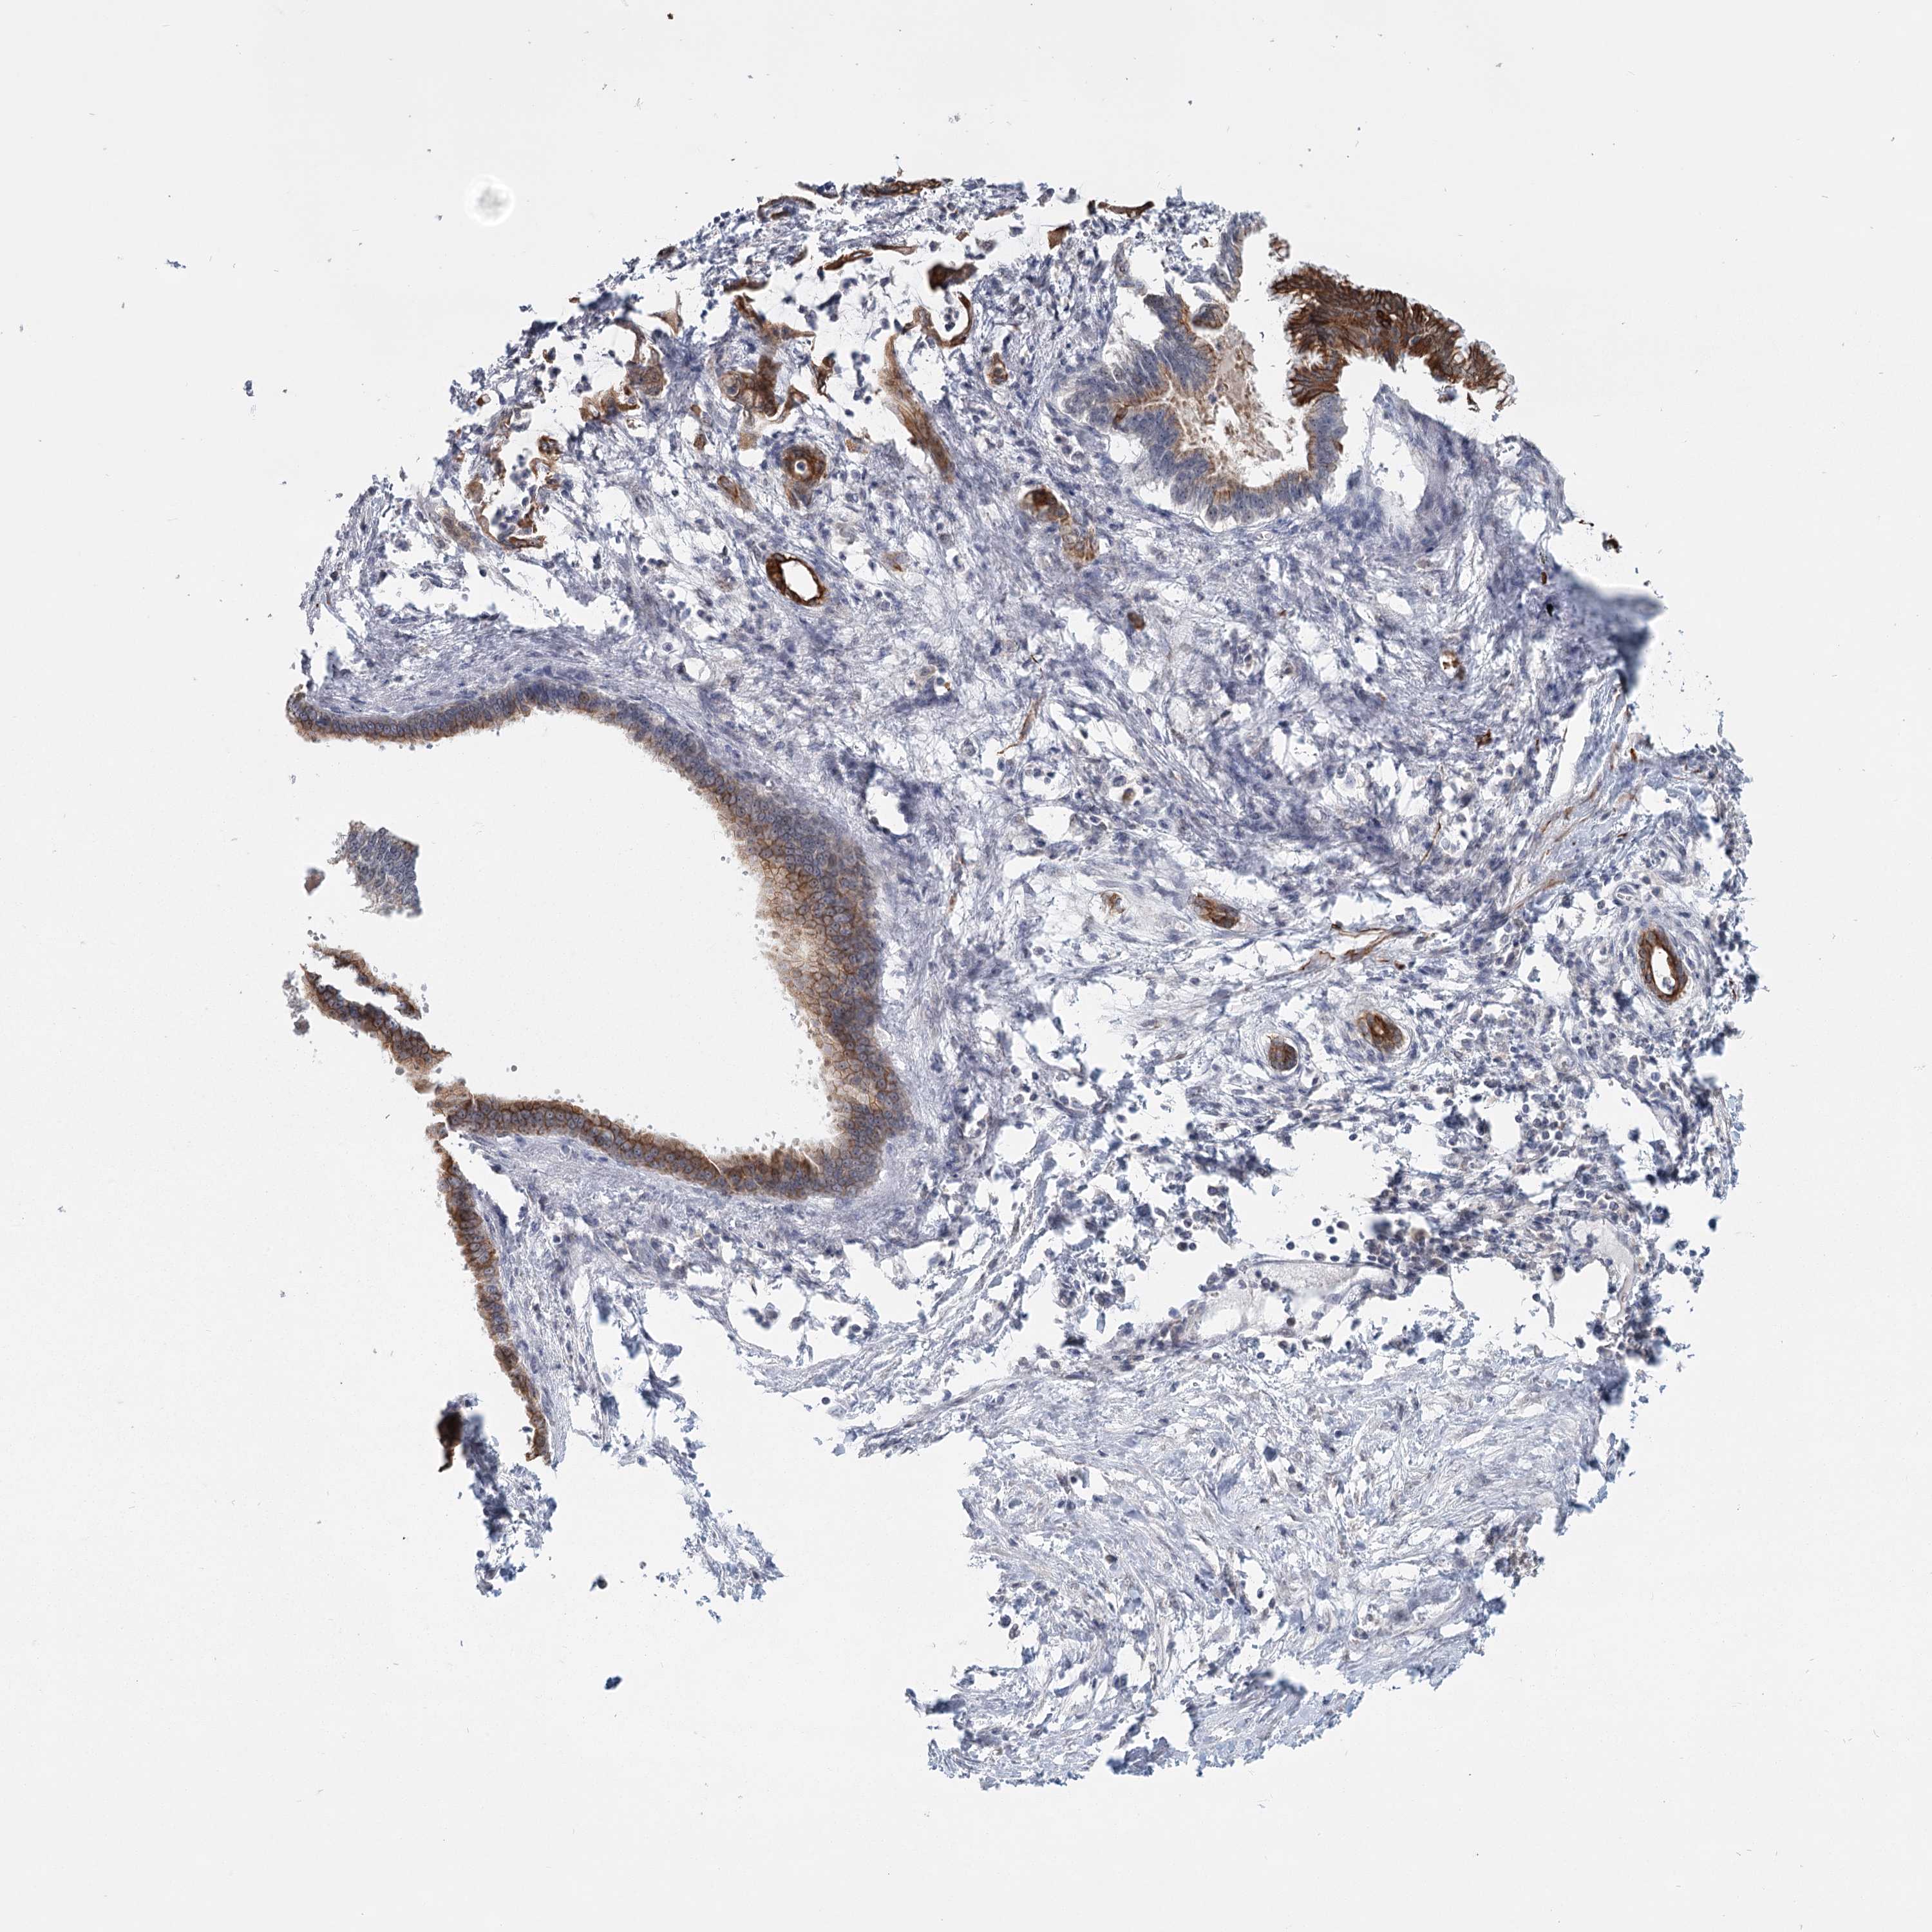

PANCREATIC CANCER - Protein expressioni

A mouse-over function shows sample information and annotation data. Click on an image to view it in a full screen mode. Samples can be filtered based on level of antibody staining by selecting one or several of the following categories: high, medium, low and not detected. The assay and annotation is described here.

Note that samples used for immunohistochemistry by the Human Protein Atlas do not correspond to samples in the TCGA dataset.

Antibody stainingi

Antibody staining in the annotated cell types in the current human tissue is reported as not detected, low, medium, or high, based on conventional immunohistochemistry profiling in selected tissues. This score is based on the combination of the staining intensity and fraction of stained cells.

Each image is clickable and will lead to virtual microscopy that enables deeper exploration of all samples and also displays staining intensity scores, fraction scores and subcellular localization as well as patient and tissue information for each sample.

Antibody HPA023187

Antibody CAB034226

Staining

High

Medium

Low

Not detected

Intensity

Strong

Moderate

Weak

Negative

Quantity

>75%

75%-25%

<25%

None

Location

Nuclear

Cytoplasmic/membranous

Cytoplasmic/membranous,nuclear

Adenocarcinoma, NOS